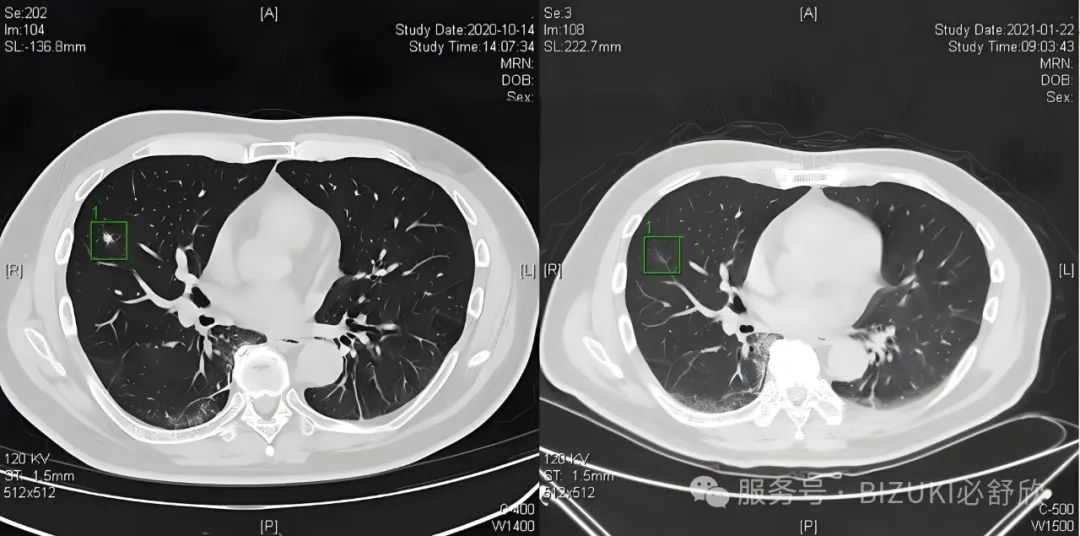

值此之际,来自日本百年医疗世家的辻村勇先生创建的保健品品牌“BIZUKI”发布了一项重磅消息:研发团队通过专利提纯技术,从生长在东西伯利亚极寒地区的野生达夫利亚落叶松提取出迄今为止全球发现的最强效、最珍贵的“万能抗氧化剂”-高精纯二氢槲皮素,CAS注册号:24198-97-8 。该地区以极冷的气温而闻名,落叶松生长在其年温差100度的自然环境中,树龄250-400年,被称为「神树]。研究发现高精纯二氢槲皮素有多种神奇功效,包括控制慢性炎症,改善血液流动。修复肺部及呼吸系统,改善消除肺结节及肺部疾病。控制过度炎症并保持血管和血液流动健康。减缓衰老过程,并延缓与生活方式相关疾病的发生。并在临床中证实:多名肺结节患者,经8周干预后,阴影CT明显缩小,长咳、气促、咳痰、呼吸不畅现象大幅改善。